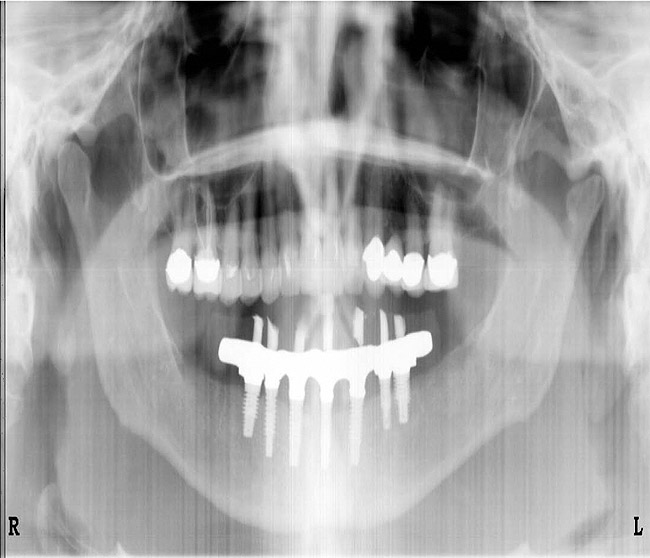

Figure 4  A crown height space > 15 mm necessitates a hybrid restoration.

Figure 4

For large-segment/full-arch fixed prostheses, the critical distance is 15 mm. If the distance from the implant platform to the occlusal table is less than 15 mm, then the prosthetic material indicated is porcelain-fused-to-metal (PFM) (Figure 3). If the distance is greater than 15 mm, then a hybrid prosthesis should be used (Figure 4).

The 15-mm measurement is important because of the physical properties of the restorative materials. Acrylic requires bulk for strength. If there is less than 15 mm of distance from the implant platform to the occlusal table, there will not be sufficient space to achieve the bulk of acrylic necessary to provide strength for the prosthesis. The unfortunate result will be continual repair of fractures for the life of the prosthesis.

Likewise, PFM restorations have difficulties when too much space is available. At dimensions greater than 15 mm from the implant platform to the occlusal table, the control of surface porosity across the metal substructure becomes difficult because of variations in cooling and heating rates across the metal,10 which in turn makes it difficult to bake porcelain to the metal substructure. The result is the high possibility of future unwanted complications of porcelain fracture.11

There is also a considerable difference in the laboratory costs for these types of prostheses. A PFM restoration requires more metal to achieve a uniform 2-mm thickness and is more technique-sensitive (Figure 5 and Figure 6). A hybrid prosthesis requires less metal and uses acrylic and denture teeth for the remaining restoration (Figure 7 and Figure 8). Understanding the impact that the 15-mm height has on which type of restoration is required gives the dentist the ability to quote a more accurate fee to the patient.